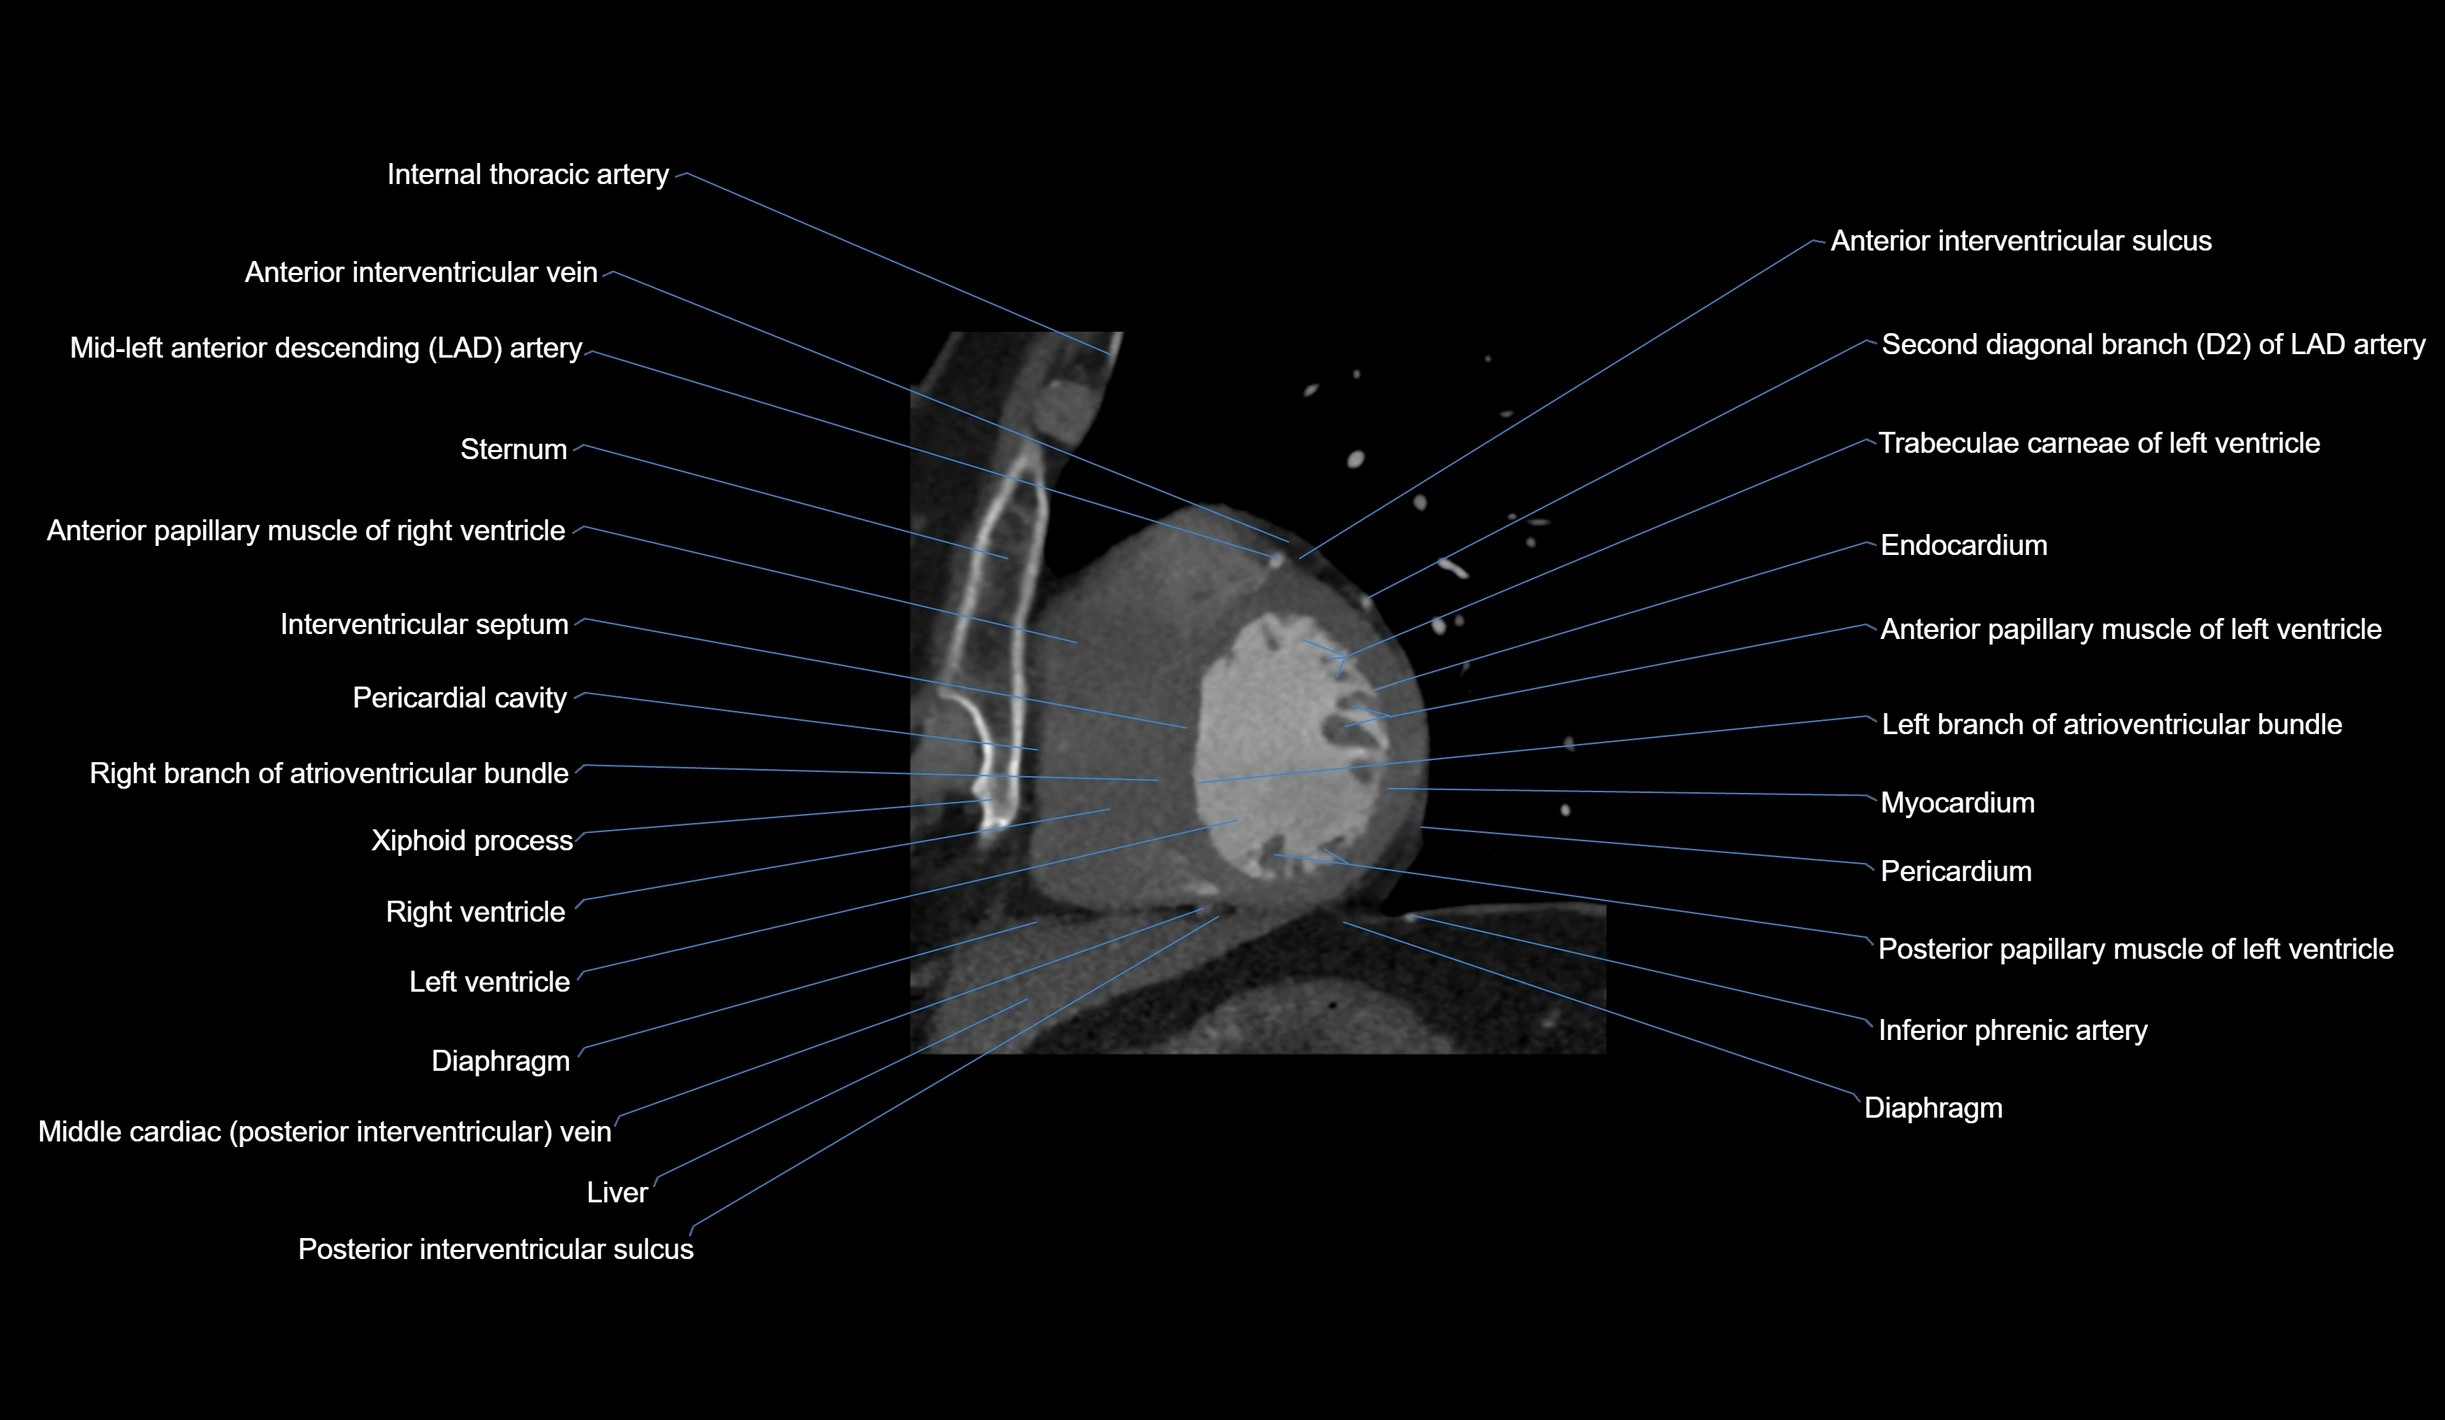

CT images